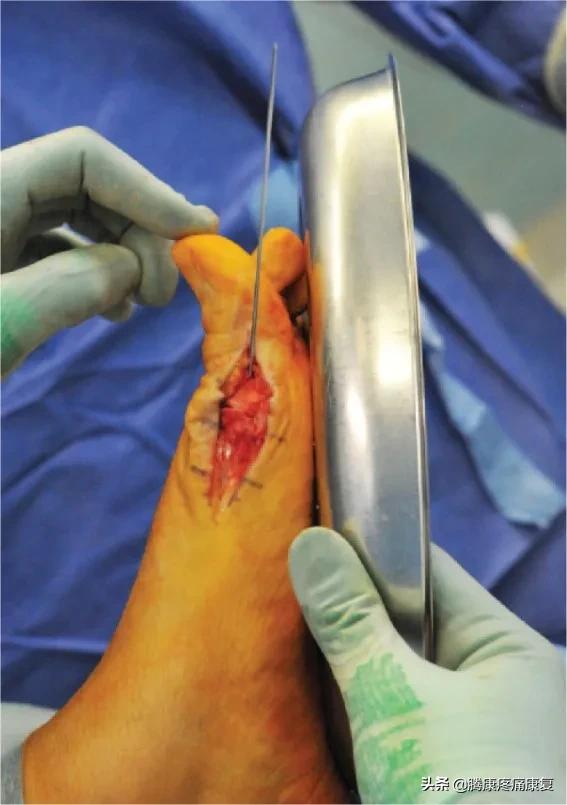

通常我们可以通过保守治疗来改善这一问题,只有当严重的疼痛限制了行动,甚至每走一步都会疼痛的时候才会考虑手术改善。